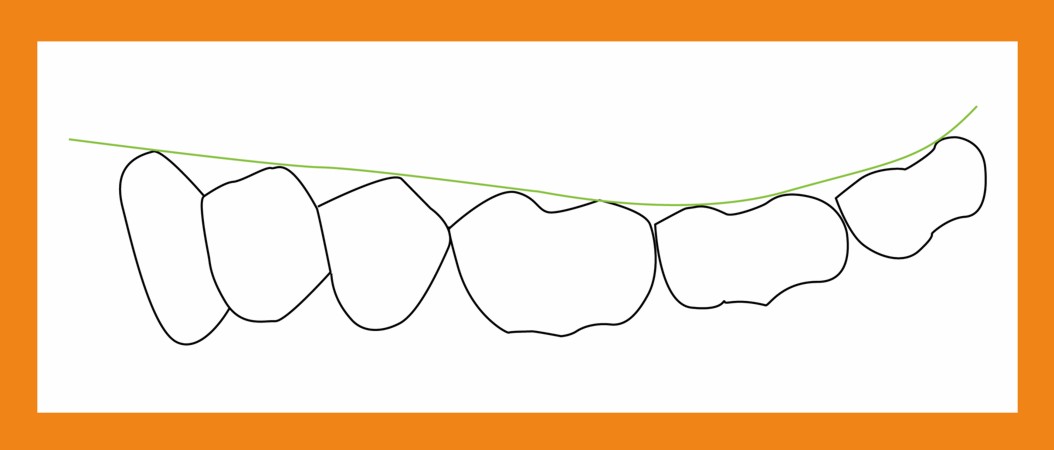

Primera Parte RESUMEN: La alta complejidad inherente a los procedimientos de Rehabilitación Oral, obligan al profesional que la ejerce a basarse en parámetros multidisciplinarios, a veces lo suficientemente intrincados que hacen imposible la práctica de la misma, sin la presencia en su mente de una clara concepción de la Oclusión. The extreme complexity of Oral Procedures, make it imperative for the working professional to rest on multidisciplinary parameters, sometimes so complex that make impossible its practice without the presence of a clear idea of Oclusion. DESARROLLO Suele ser sumamente árido el abordaje de un tema como Oclusión, desde la perspectiva de nuestro diario trabajo ,con todo el strees que este conlleva, con toda la lucha que significan citas, honorarios, diferentes personalidades de los pacientes, inquietudes de los mismos, etc. «LA MEJOR OCLUSIÓN ES LA QUE TIENE LA MEJOR DESOCLUSIÓN» Básicamente, podemos como desde hace ya muchos años se viene haciendo; clasificarlos en: A)Determinantes Posteriores (fijos) Más contemporáneamente, en: I-Mecanismos Primarios: A.T.M. GUIA ANTERIOR INCLINACIÓN DEL PLANO OCLUSAL CURVA SAGITAL DE SPEE FORMA DE LA ARCADA III-Mecanismos Elementales CRESTAS TRIANGULARES INTERNAS Analicemos cada uno de ellos: Es evidente, que la reproducción de las características de la A.T.M., en nuestro aliado fundamental, el Articulador; es imprescindible. Partiendo de la premisa de obtener una OCLUSIÓN MUTUAMENTE PROTEGIDA, para luego arribar al concepto de OCLUSIÓN MUTUAMENTE COMPARTIDA, concepto este que desarrollaremos durante el transcurso de las distintas entregas, analizaremos cada uno de los FACTORES DETERMINANTES DE LA OCLUSIÓN. El primero de ellos, por ser fijo e invariable, solo diremos que: son sus INCLINACIONES PLANARES, o sea : A-INCLINACIÓN DE LA TRAYECTORIA CONDILEA C-BENNET INMEDIATO articuladores totalmente ajustables) D-DISTANCIA INTERCONDILAR. En cuanto a la GUÍA ANTERIOR, mecanismo primario y por supuesto anterior, provee al cuerpo mandibular; del camino a recorrer durante las excursiones protrusivas y lateralidades, a través del vínculo entre las piezas dentarias anteriores, superiores e inferiores. En un corte sagital, podemos observar la relación entre estos donde vemos que se vinculan sin entrar en un contacto franco, sino más bien en una relación de vencindad muy intima a la que llamamos: PUNTO DE ACOPLAMIENTO. Otros factores fundamentales de la GUÍA ANTERIOR son : A-ALTURA FUNCIONAL B-PUNTO DE ACOPLAMIENTO En cuanto a los SURCOS, sabemos que durante una Transtrusión, las cúspides fundamentales generan surcos sobre las piezas que antagonizan. Dichos surcos proveen de una vía de escape a las cúspides antagonistas para evitar colisiones, con las indeseables fuerzas laterales cuya gravedad ya conocemos. MECANISMOS SECUNDARIOS La CURVA FRONTAL DE WILSON, se observa invertida a nivel de los caninos y de los primeros premolares. El PLANO OCLUSAL, en realidad no es ningún plano, sino la sumatoria de muchos MICROPLANOS, los cuales individualmente pueden constituir factores presentes en la OCLUSIÓN, pero auténticos problemas para la DISCLUSIÓN. La CURVA SAGITAL DE SPEE, denominada originariamente de BALKWIL-SPEE, fue concebida como una curva. El cuarto factor SECUNDARIO: el ANCHO DE LA ARCADA, es evidente que variando los ejes de rotación , alrededor de las diferentes distancias ;cambiará la dirección de los escapes (surcos), de los elementos que en el se muevan (cúspides). MECANISMOS ELEMENTALES Los CUATRO NIVELES DE OCLUSIÓN y las CRESTAS TRIANGULARES INTERNAS, constituyen de por si, la herramienta ejecutora de las funciones gnáticas. A- ELEVACIONES 1-Puntas Cuspídeas B-DEPRESIONES 1-Fosas SURCOS DE DESARROLLO De las CRESTAS TRIANGULARES INTERNAS, acentuamos su importancia en ellas dado que son las efectoras finales de la molienda, y su triangularidad debe tener su base partiendo del surco y su vértice terminando en la Punta Cuspídea, condición importante para evitar colisiones durante la transtrusión (movimiento de lateralidad ). EFECTOS DE LA VARIABILIDAD DE LOS FACTORES DETERMINANTES DE LA OCLUSÍON Cada uno de los determinantes influye aumentando o disminuyendo tanto la DESOCLUSIÓN como la ALTURA CUSPÍDEA INCLINACIÓN DE LA TRAYECTORIA SAGITAL INCLINACIÓN DEL PLANO OCLUSAL RADIO DE CURVATURA DE LA ÁNGULO DE LA TRAYECTORIA ALTURA DEL PUNTO DE LATERO SURTRUSIÓN / MOV. DE BENNET INMEDIATO CURVA FRONTAL DE WILSON SURCOS BIBLIOGRAFÍA Dibujos y esquemas tomados del libro: Oclusión Orgánica…un camino hacia la Rehabilitación Oral. 1)William Mc Horris,B.S.,D.D.S. Oclusión. Con especial énfasis sobre :El rol funcional y parafuncional de los dientes anteriores. 2)Von Spee , Craff(Anatomista alemán, describió la curva de compensación de la articulación de molares y premolares).CURVA DE SPEE 1.89 3)Stuart,D.»Some aspects of the inervation teeth.»Procedings of Royal Society of Medicine.20:1675,19274)Muhleman,H. y Savdir,S»Tooth movility-its causes and significance»Journal of Periodontology ,36:153,Marzo ,Abril,1965. 4)Muhleman,H. Y Savdir,S»Toothmovility its causes and significance» Journal of Periodontology,36:153,marzo,abril,1965. 5-Oclusión y Diagnóstico en Rehabilitación Oral. 6-Anatomia Odontológica. -A contribution to the study of the movementes of the mandible. 8-Celenza F.W, Nadeskin J.F.,Oclusión.Situación actual. 9-D´Amico 10-Dawson P.E. 11-Huffman -Regenos. 12-Hobo S.-Takayama H.A. 13-Lucia V.O 14-Mc Horris. 15-Mc Horris. 13-Posselt U. 16-Stuart C. 17-Vartan Veshnilian

Es recta en el segundo premolar y comienza a ser de concavidad superior a la altura del primer molar, acentuándose hacia atrás para terminar concibiéndose al cóndilo como un cuarto molar.

Sin embargo, si observamos con atención una vista sagital, veremos como la cúspide distal del primer molar; desciende, constituyendo hasta la misma una auténtica recta, y a partir de ella una curva que asciende hasta la cúspide distal del tercer molar.

Se ha dicho, que dicha cúspide descendente, constituiría una mecanismo SUPLETORIO de DESOCLUSIÓN, en el caso de fallar la DESOCLUSIÓN CANINA.